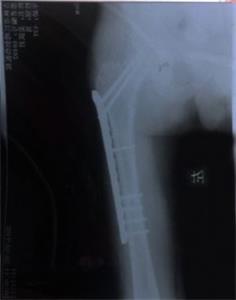

'姜跃军腿部术后照片'

姜跃军腿部术后照片

一直由姜跃军赡养的岳母患有肝病,因担心女婿而吐血病危住院。姜恳请“610”人员让他回家探望岳母,可他们完全不计人伦,不顾亲情与孝道地说:死了也不准!别说是岳母呀,就是亲妈死了也许能有一点点可能!万般无奈之下,姜跃军于9月20日从洗脑班二楼跳下,导致大腿骨粉碎性骨折。妻子得知消息去医院护理丈夫,结果遭国保大队张学涛、南城派出所曹凤坤、夏春林等大量警察绑架并拘留(拘留结束后又直接转到吉林市与舒兰市两处洗脑班继续迫害)。